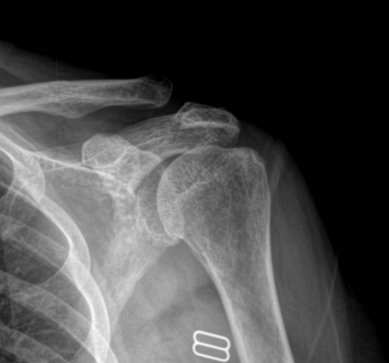

¹æ»ç¼± °Ë»ç : ¾î±ú ÀÜ¸é »çÁø¿¡¼ ´ë°áÀýÀÇ ¹Ì¼¼ÇÑ °ñ±Ø°ú °æÈµÈ ¼Ò°ßÀ» º¸ÀÌ°í °ßºÀ ÇÏ´ÜÀÇ °æÈ ¼Ò°ß ¹× ¿À±¸µ¹±â °ßºÀÀÎ´ë ºÎÂøºÎ °ñ±ØÀ» º¸¿© ¸¸¼ºÀûÀÎ Ãæµ¹ÀÌ ÃßÁ¤µÊ. ¿ÜÀü½Ã Àü¸é »çÁø¿¡¼ ´ë°áÀýÀÌ °ßºÀÇÏ´Ü¿¡ Á¢ÃËÇÏ´Â ¸ð½ÀÀÌ °üÂûµÊ.

Ä¡ ·á : ÅëÁõ °¨¼Ò¸¦ À§ÇÑ °üÀý³» ÁÖ»çÄ¡·á ÃÊÀ½ÆÄ »çÁø 13, ÷ºÎµ¿¿µ»ó 3¹ø Âü°í. °í Âû : Ãæµ¹ÁõÈıºÀº »ó¿Ï°ñÀÇ ´ë°áÀýÀÌ °ßºÀ°ú Ãæµ¹ÇÏ´Â ÁõÈıºÀ¸·Î ´ë°³ ÆÈÀ» À§·Î µå´Â Á÷¾÷À̳ª ½ºÆ÷Ã÷ Ȱµ¿À» °úµµÇÏ°Ô ÇÑ´Â »ç¶÷µé¿¡°Ô¼ ¸¹ÀÌ ¹ß»ýÇÒ ¼ö ÀÖ´Ù(»çÁø 1).

Ãæµ¹ÀÌ ÁøÇàµÇ¸é ´Ü¼ø¹æ»ç¼± ÃÔ¿µ¿¡¼µµ Ãæµ¹ÀÇ ÈçÀûÀ» ¹ß°ßÇÒ ¼ö ÀÖ´Ù. ´Ü¼ø¹æ»ç¼± ÃÔ¿µ¿¡¼ ´ë°áÀýÀ̳ª °ßºÀÀÇ °æÈ¼º º¯È(sclerotic change) ¶Ç´Â °ñ±Ø, ´ë°áÀûÀÇ °ñ °á¼ÕÀÌ °üÂûµÇ¸é Ãæµ¹ÀÌ ¸¸¼ºÀûÀ¸·Î ÁøÇàµÇ¾úÀ½À» ½Ã»çÇØÁØ´Ù. °ßºÀ¼â°ñ°üÀý ÇÏ´ÜÀÇ °ñ±ØÀ̳ª caudal tilt ÃØ¿µ¿¡¼ º¸ÀÌ´Â °ßºÀÀÇ °ñ±ØÀ» °üÂûÇϸé Ãæµ¹ ¹ß»ý °¡´É¼ºÀ» ÃßÁ¤ÇÒ ¼ö ÀÖ°í ¿À±¸µ¹±â°ßºÀÀÎ´ë °ßºÀ ºÎÂøºÎ¿¡¼ º¸ÀÌ´Â °ñ±ØÀº ȸÀü±Ù°³ ÆÄ¿À» °·ÂÈ÷ ½Ã»çÇÏ´Â ¼Ò°ßÀ̰í ÀÌ·± °æ¿ì ´ë°³ º¸Á¸Àû Ä¡·á¿¡ ¾çÈ£ÇÑ È£ÀüÀ» º¸ÀÌÁö ¾Ê´Â´Ù. ÀüÈĹæ»çÁø¿¡¼ critical shoulder angleÀ» °üÂûÇÑ´À ½À°üµµ ¸Å¿ì À¯¿ëÇÏ´Ù(»çÁø 4).